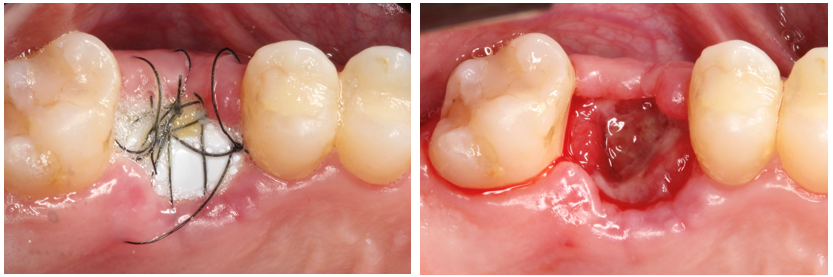

Paciente C.B.F.J., 33 anos, leucoderma, não-fumante e em boas condições de saúde sistêmica, relatou sensibilidade dolorosa durante mastigação no elemento 26, que já possuía tratamento endodôntico, pinos metálicos intrarradiculares e coroa metalocerâmica (Figura 1). Foi solicitada tomografia computadorizada de feixe cônico, na qual a imagem sugeriu fratura radicular na região da furca, descontinuidade óssea da cortical de seio maxilar e opacificação parcial do seio maxilar esquerdo (Figura 2). Foi realizada a exodontia e pôde-se confirmar a comunicação oroantral (Figura 3). Após curetagem do alvéolo, sem preocupação em curetar e remover a lesão cística sinusal, uma barreira reabsorvível foi recortada e posicionada no fundo do alvéolo para obliterar a descontinuidade óssea e impedir que células de tecido mole oriundas da cavidade sinusal invadissem a região alveolar (Figura 4). O alvéolo foi preenchido totalmente por coágulo sanguíneo do paciente (Figura 5) e o alvéolo foi selado por uma barreira não-reabsorvível (Figura 6), impedindo a invasão de fibroblastos do tecido gengival para dentro do alvéolo. Após duas semanas, a barreira estava estável e, então, foi removida, desnudando um tecido de granulação osteoblastogênico (Figura 7).